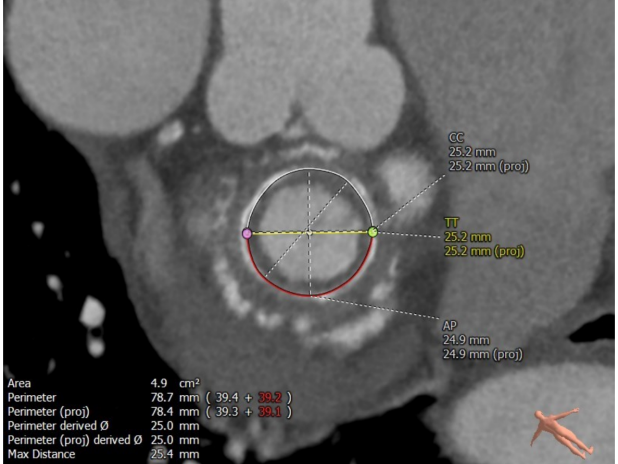

术前经详尽评估患者病情,通过CT重建测量瓣环直径、左室流出道面积。结合之前外科换瓣手术入路,决定采用经心尖途径行二尖瓣“瓣中瓣”手术。术中选用25# Renato®球扩式瓣中瓣,顺利通过心尖途径植入。手术过程顺利,几乎无出血。最终瓣中瓣植入位置理想,功能表现出色,左室造影及经食道超声观察无明显瓣中及瓣周反流。二尖瓣峰值流速由术前2.5m/s降至1.5m/s,平均跨瓣压差由11mmHg降至2.6mmHg。

毁损生物瓣瓣架结构 瓣环内径测量